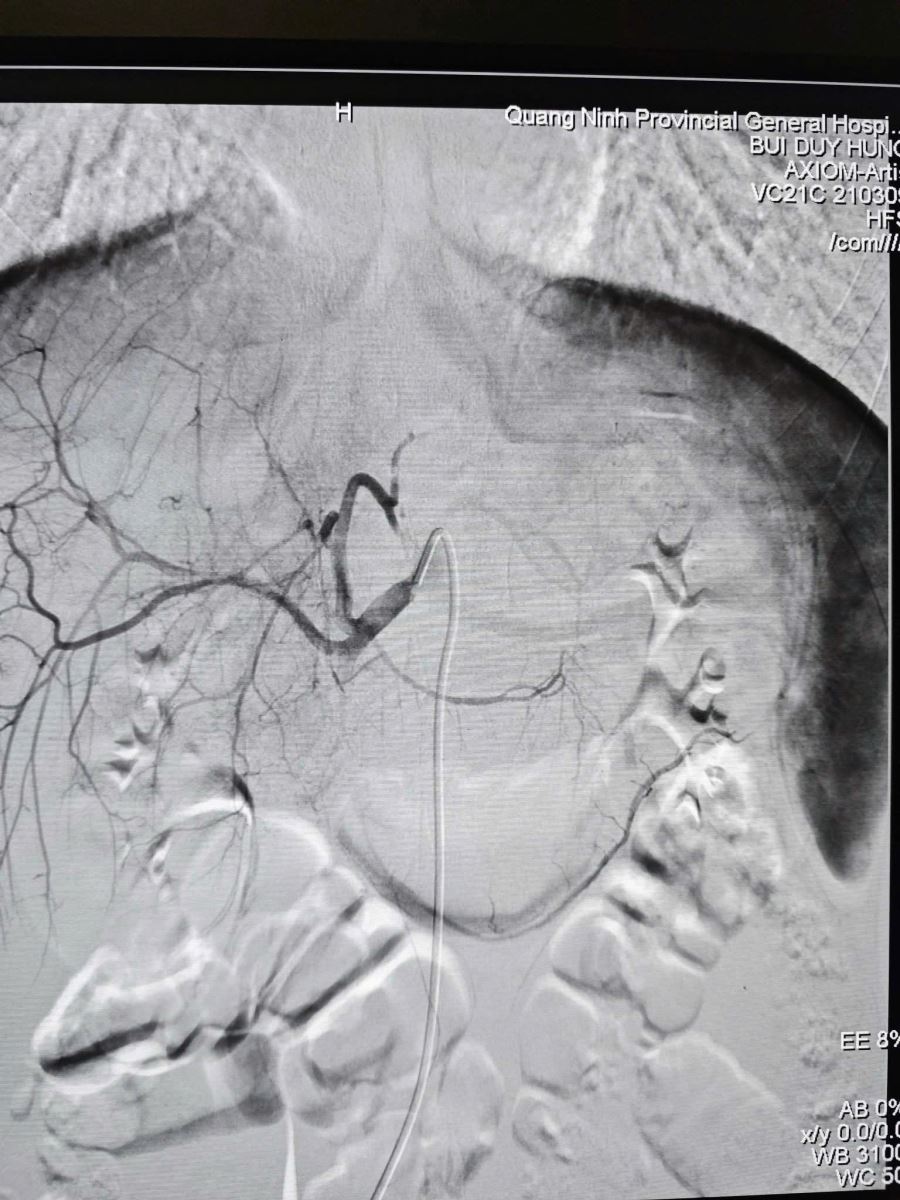

Hình ảnh sau nút mạch điều trị chấn thương gan, ổ chảy máu đã được nút tắc.

Sau 60 phút, ca can thiệp thành công tốt đẹp, hình ảnh chụp kiểm tra cho thấy điểm chảy máu đã được cầm hoàn toàn. Huyết động bệnh nhân ổn định và được chuyển hậu phẫu theo dõi với tiên lượng phục hồi. Thành công của ca bệnh khẳng định hiệu quả của mô hình hoạt động đồng bộ, năng lực chẩn đoán tại chỗ nhanh, chính xác ngay từ đầu nhờ CT Scanner và nhân lực chất lượng làm chủ kỹ thuật nút mạch giúp xử trí chấn thương nhẹ nhàng, hiệu quả cao. Sự đồng bộ và hiệp đồng tác chiến giữa hai cơ sở đang ngày càng khẳng định Bệnh viện Đa khoa tỉnh Quảng Ninh là địa chỉ tin cậy, mang lại cơ hội sống cao nhất cho người bệnh trong các tình huống cấp cứu tối khẩn./.